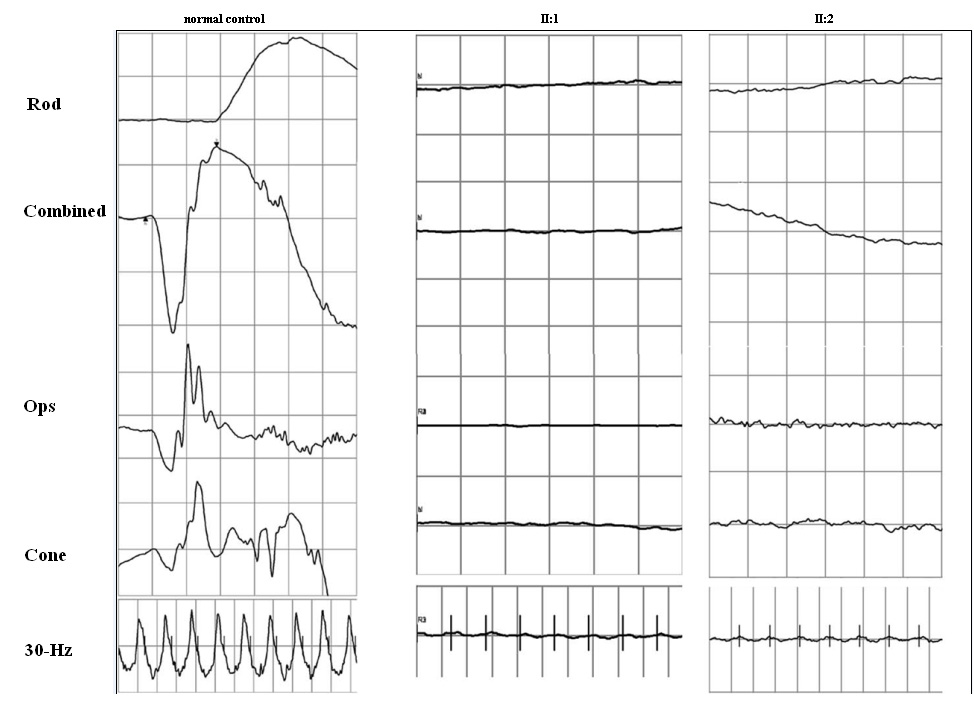

Figure 4 of Xu, Mol Vis 2012; 18:744-750.

Figure 4. The figure depicts the electrophysiological changes of the two Chinese Leber congenital amarousis (LCA) patients. All recording conditions refer to International Society for Clinical Electrophysiology of Vision (ISCEV).